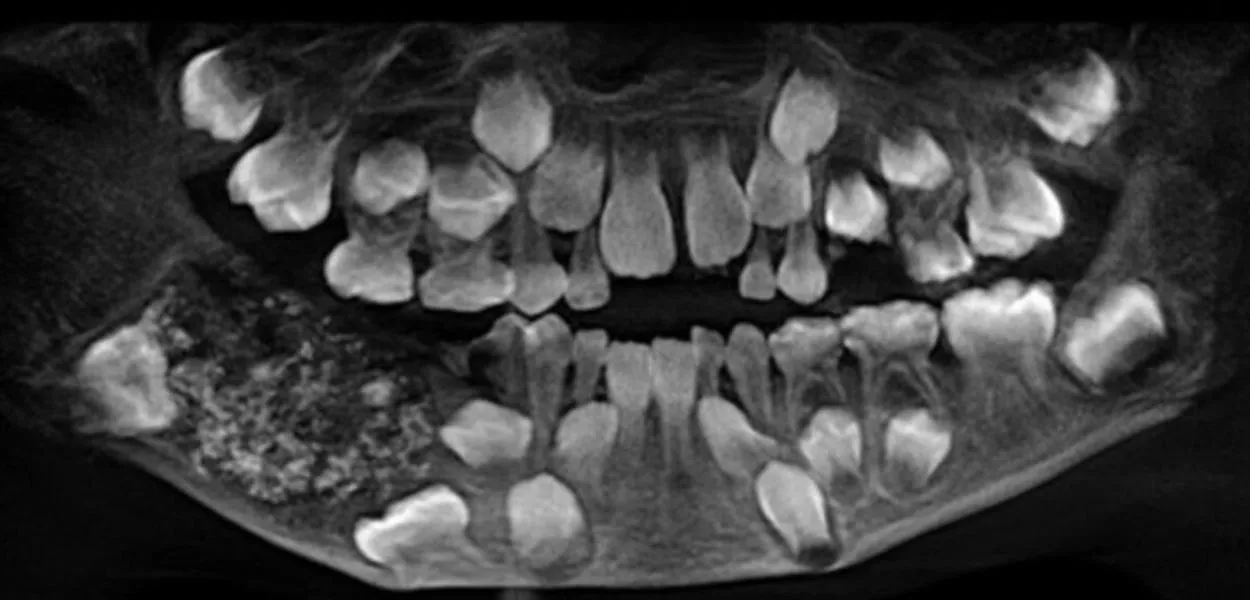

Caso raro de odontoma composto surpreendeu médicos em Chennai, na Índia, e entrou para a história da odontologia

Menino de 7 anos tem 526 dentes removidos em cirurgia na Índia

Após investigação, os médicos constataram tratar-se de um odontoma composto